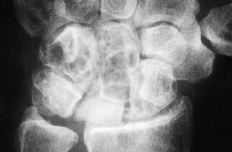

Figura 4. Radiografía posteroanterior de muñeca donde se muestra una luxación cubital del implante junto con un colapso carpiano y una traslación cubital.

Figura 5. En la radiografía de perfil se aprecia la inestabilidad en DISI del implante.

ABFigura 6. Imágenes líticas intraóseas de predominio hueso grande-piramidal. A: Radiológica. B: Tomografía computerizada.